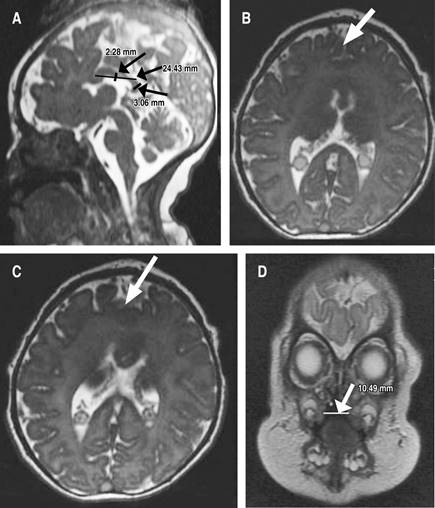

Debido al diagnóstico de HPE, inmediatamente posterior a su nacimiento se tomaron imágenes de resonancia magnética, que revelaron anomalías de la línea media caracterizadas por fusión interhemisférica parcial de los lóbulos frontales, asociada con la ausencia de la rodilla del cuerpo calloso, que tiene una longitud de 24.4 mm, cuerpo de 2.3 mm y esplenio de 3.1 mm, condicionando disminución de la amplitud de los huecos frontales, pero con núcleos grises conservados (Figura 1).

Figura 1: Sintelencefalia demostrada por resonancia magnética nuclear. A) Ausencia de la rodilla del cuerpo calloso, este cuenta con un tamaño de 24.4 mm (normal 5.1 ± 1.0 mm), cuerpo de 2.3 mm (2.3 ± 0.6 mm) y esplenio de 3.1 mm (normal 3.7 ± 0.6 mm), lo que condiciona una disminución en la amplitud del receso frontal, cerebelo y tallo encefálico de morfología e intensidad preservada. Sistema infratentorial y espacio subaracnoideo normal. B y C) Anormalidades de línea media caracterizadas por fusión parcial de los lóbulos frontales. D) Ausencia en la fusión del paladar duro que comunica con la cavidad nasal derecha, ausencia de fusión de labio superior derecho, defecto de 10.5 mm. Nota: estudio realizado el día del nacimiento de la paciente.